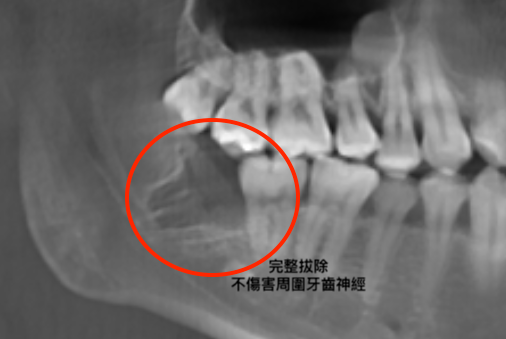

手術過程

由專科醫師主刀,術前先說明治療過程及注意事項,簽署麻醉同意書,並在局部麻醉下快速精準拔除患齒,清理並縫合傷口。 依據傷口情況,醫師有時會建議放置膠原蛋白以加速傷口癒合。此項治療大多為自費項目,可與醫師討論後決定是否進行。